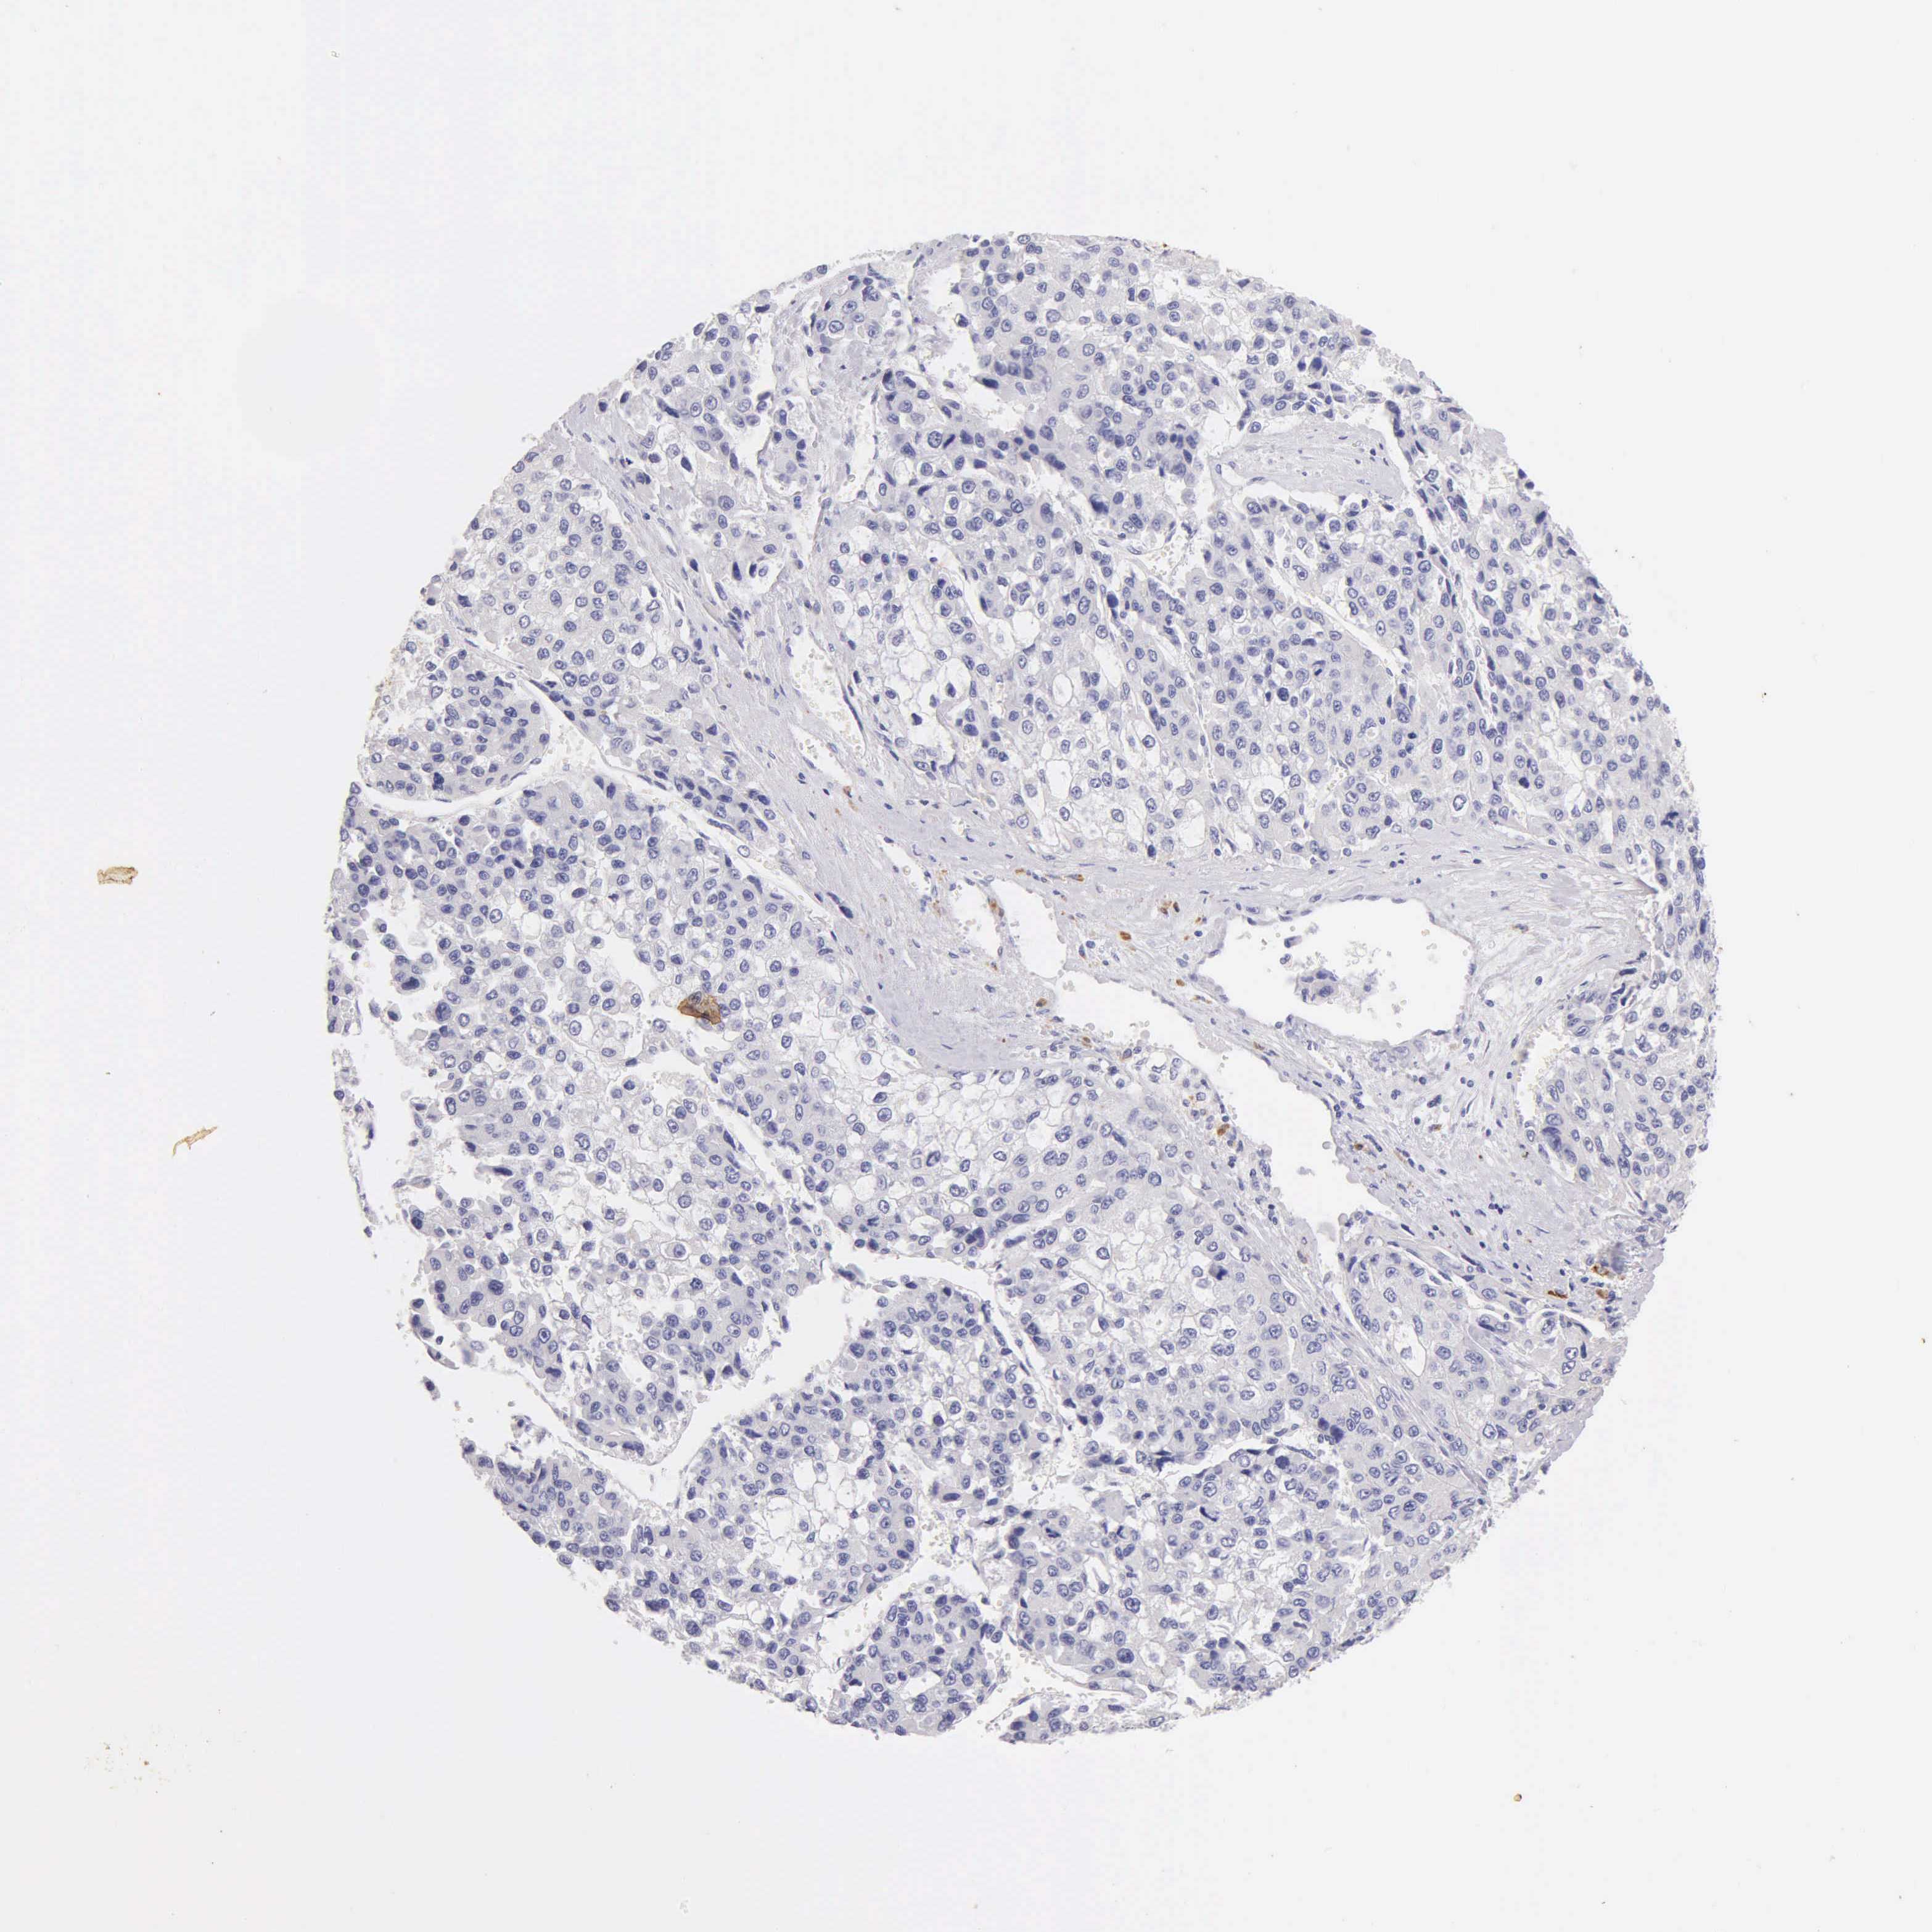

LIVER CANCER - Protein expressioni

A mouse-over function shows sample information and annotation data. Click on an image to view it in a full screen mode. Samples can be filtered based on level of antibody staining by selecting one or several of the following categories: high, medium, low and not detected. The assay and annotation is described here.

Note that samples used for immunohistochemistry by the Human Protein Atlas do not correspond to samples in the TCGA dataset.

Antibody HPA000452

Antibody HPA023040

Antibody CAB000134

Staining

High

Medium

Low

Not detected

Intensity

Strong

Moderate

Weak

Negative

Quantity

>75%

75%-25%

<25%

None

Location

Nuclear

Cytoplasmic/membranous

Cytoplasmic/membranous,nuclear

Carcinoma, Hepatocellular, NOS

Cholangiocarcinoma